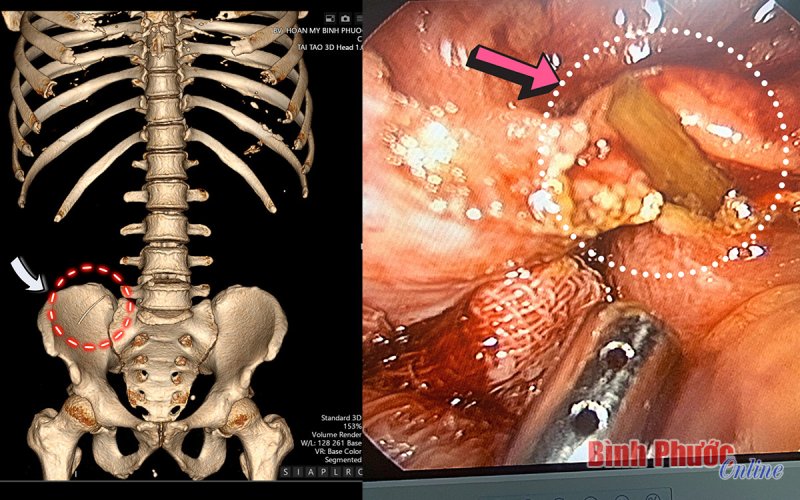

Bình Phước: Người đàn ông bị xương cá đâm thủng thành ruột BPO - Sau gần 4 ngày phẫu thuật, đến nay tình trạng sức khỏe của bệnh nhân N.V.H, 45 tuổi, thành phố Đồng Xoài, tỉnh Bình Phước đã ổn định và dự kiến xuất viện...

Hội thảo và trải nghiệm dòng máy CT hiện đại nhất hiện nay BPO - Sáng nay 20-4, Bệnh viện Hoàn Mỹ Bình Phước tổ chức hội thảo và trải nghiệm dòng máy CT mới nhất hiện nay. Dự hội thảo có Ủy viên Ban Thường vụ Tỉnh ủy,... 20/04/2022 12:10